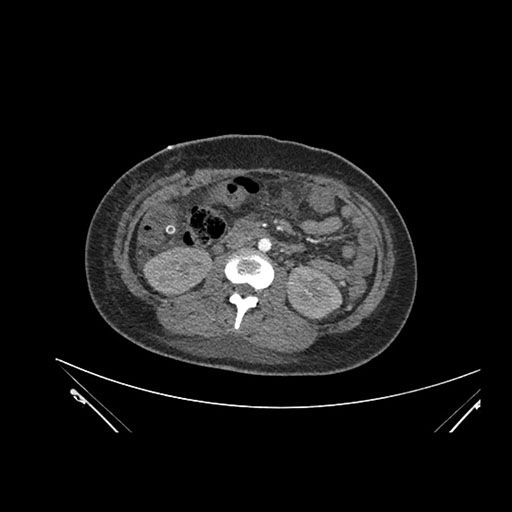

Imaging Analysis

Look through the patient's CT scan to identify any areas of concern for the necessary procedure.

Based on initial findings, which issue(s) would you be most concerned about?